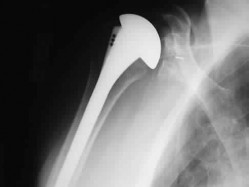

A 72-year-old female undergoes a reverse total shoulder arthroplasty (rTSA) for severe rotator cuff tear arthropathy. Compared to the native anatomic shoulder, which of the following best describes the biomechanical alteration of the center of rotation following a standard Grammont-style rTSA?

Explanation